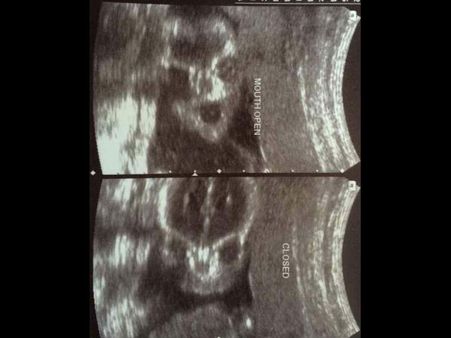

Picture#4 The Poser!

This baby sure must be a born poser and learnt it in the womb! Check out on these two different ultrasounds, where he is freaking us out with his mouth open in one of the scans and closing the mouth in the other! We bet, the little one knew he was being clicked!